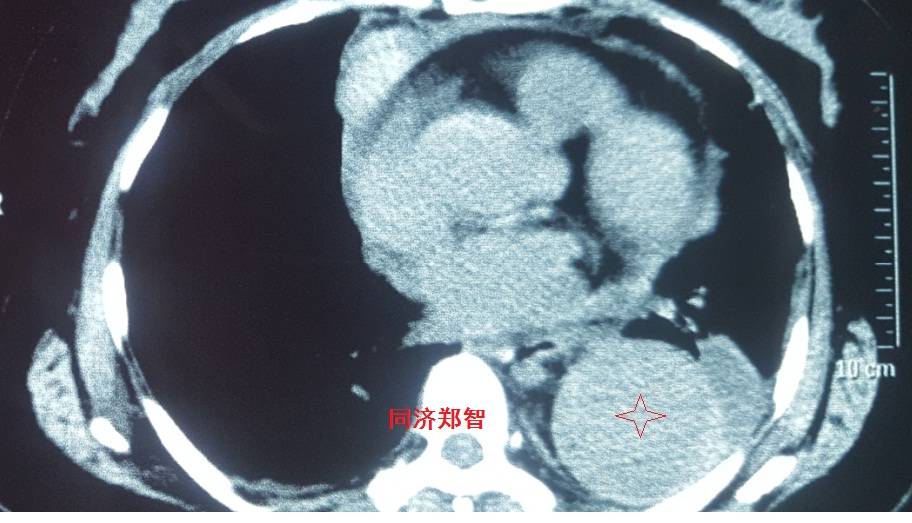

病例七

平扫CT提示升主动脉及降主动脉内膜片,CTA证实为A型主动脉壁间血肿。